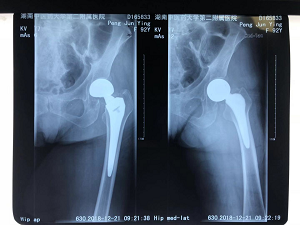

2018年12月,我院骨伤三科在董克芳主任带领下,连续为8位85岁以上老人实施了人工关节置换手术,平均年龄达90岁,最高者97岁,最低的也有86岁,患者均在10天以内单独扶拐下床步行,最大限度地让患者避免了长期卧床带来的并发症。

娄底97岁患者术后5天即可在助步器辅助下行走

董克芳主任同时表示,此类患者的手术本身围手术起风险较高,需要医生护士更加细心、耐心,同时更需要患者及家属真正正确认识病情,理解风险。有些时候甚至需要多科联合,才能最大限度的降低风险,帮助患者度过手术期。对于手术医师来说,要最大化缩短手术时间,减少失血,降低创伤。本组患者,我们改进了手术入路,从臀中肌肌间隙入路,尽量减少肌肉损伤,减少手术创伤,同时缩短切口,平均手术时间45分钟,失血量仅仅100-150毫升,可以说尽到了最大化的微创,其中2个病例术后未放置引流管。